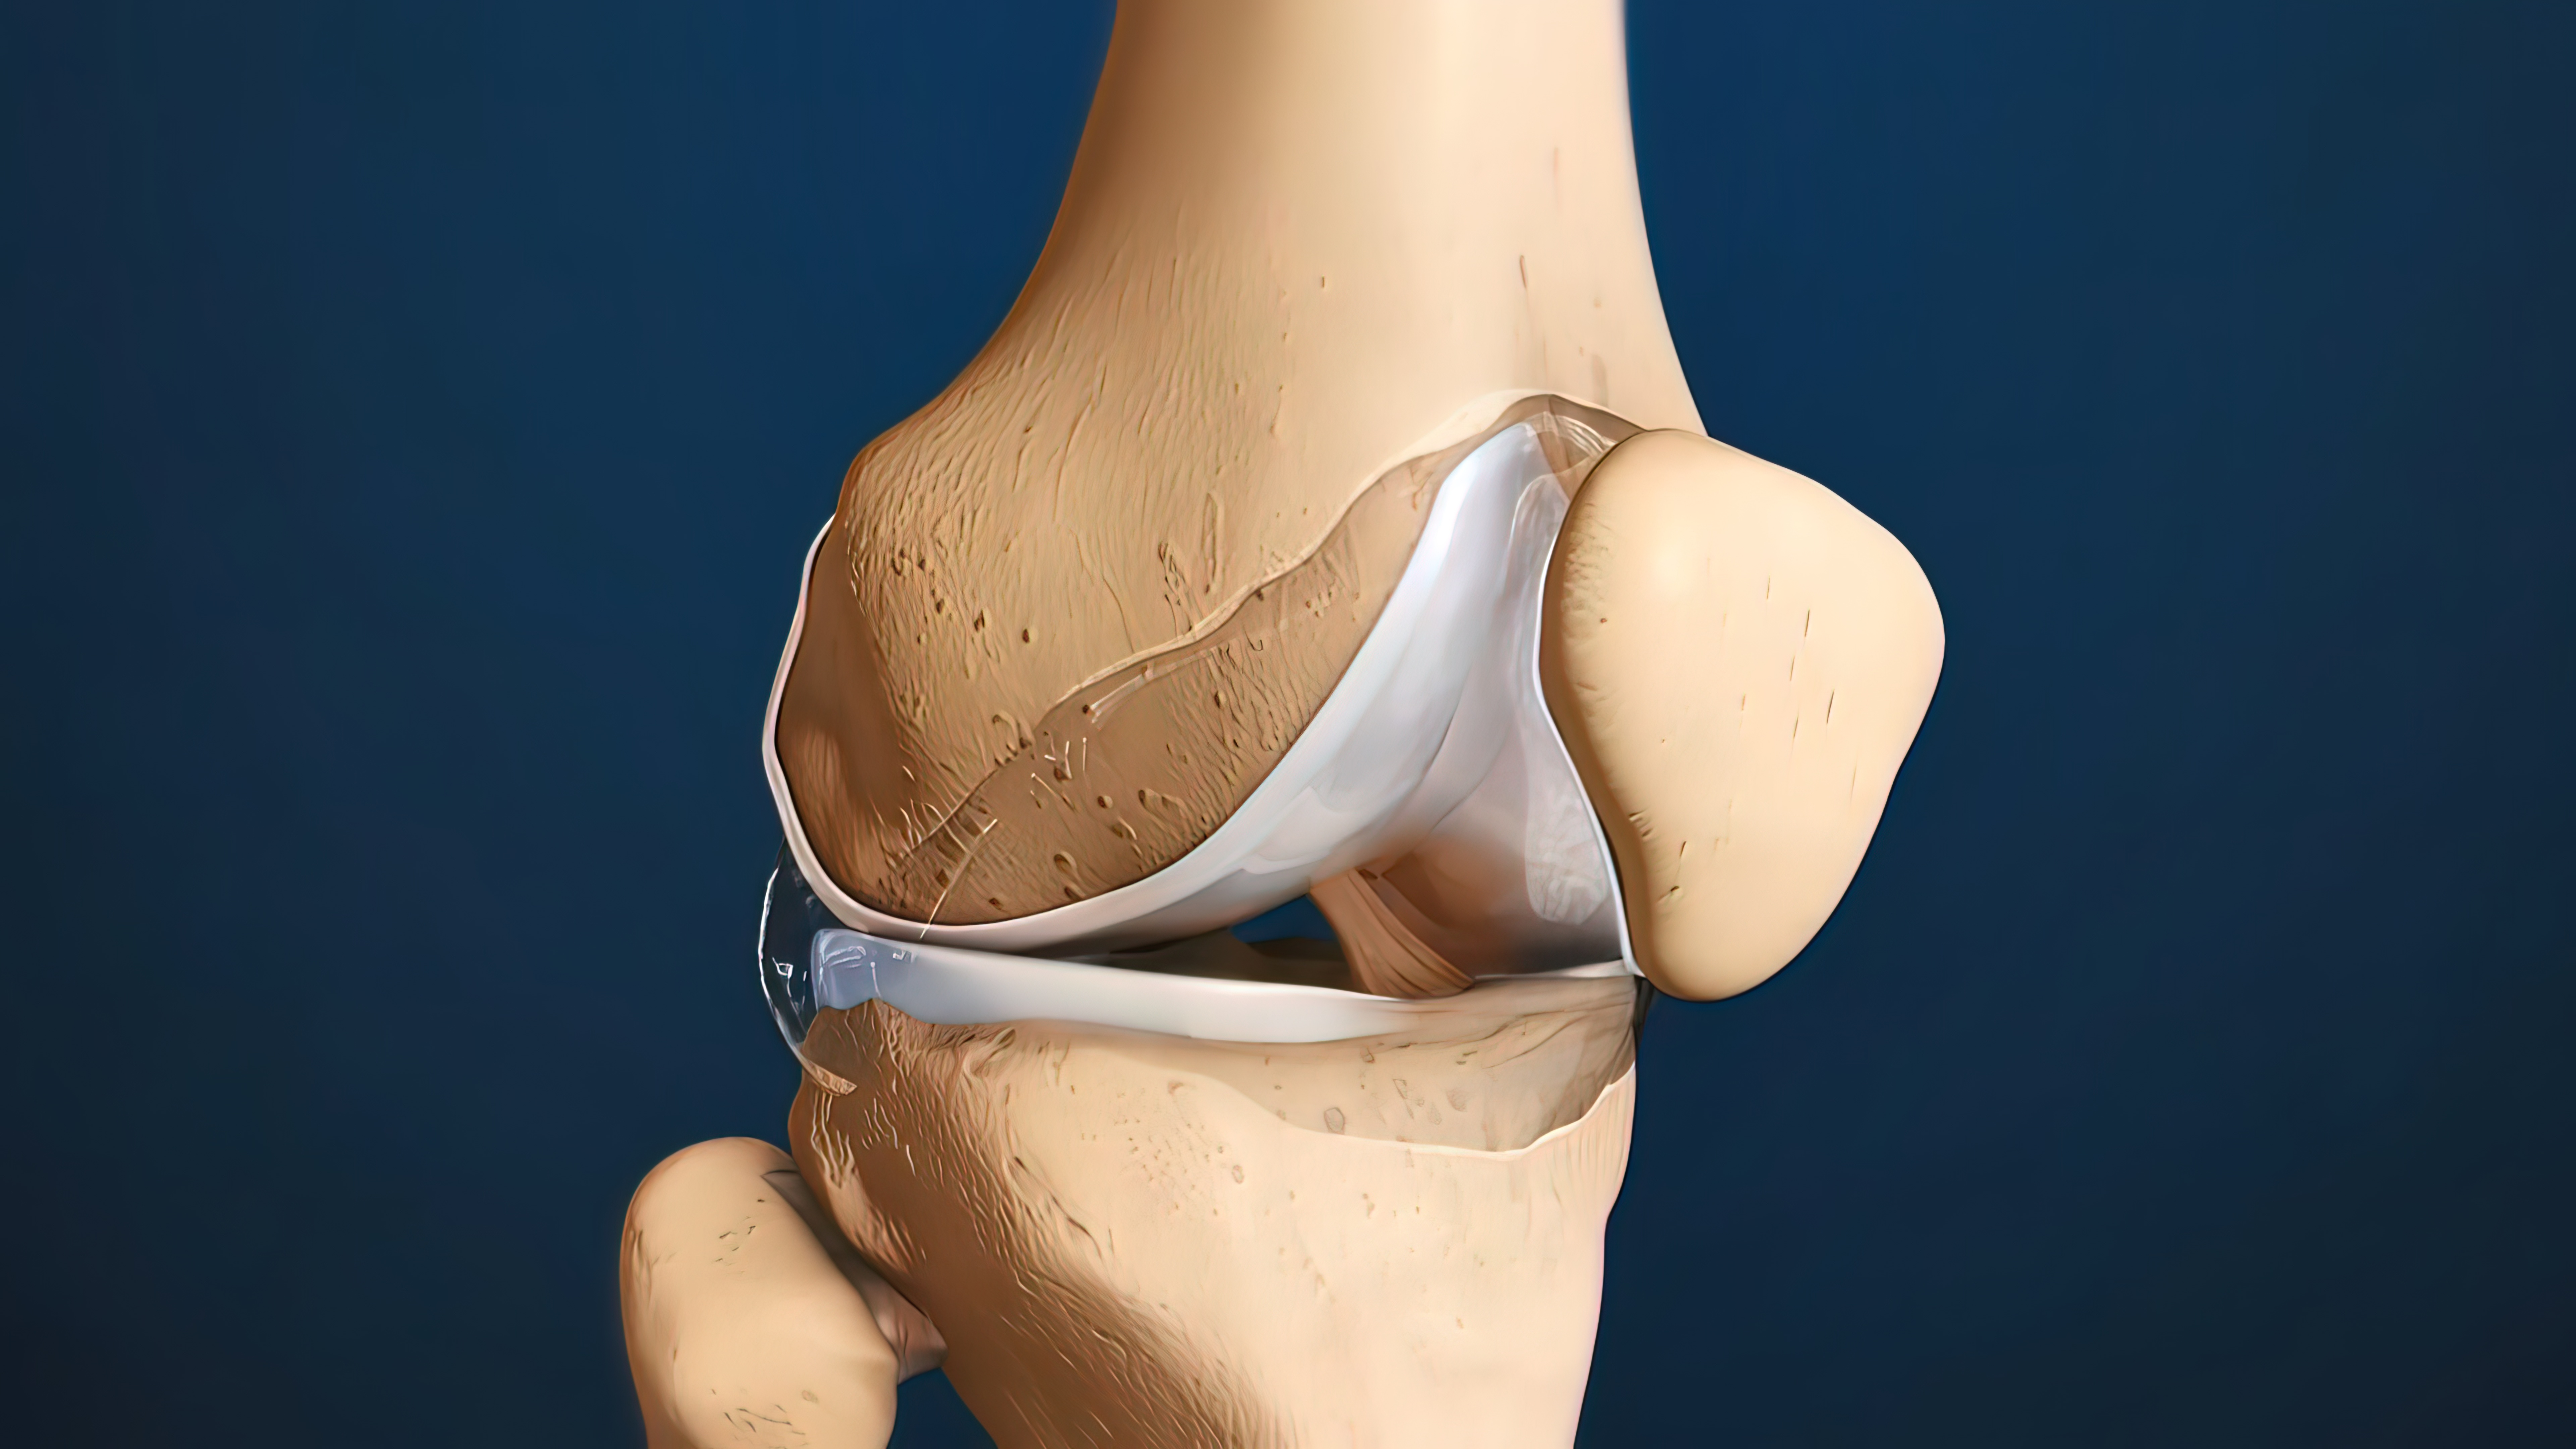

影响关节活动度的元凶之一